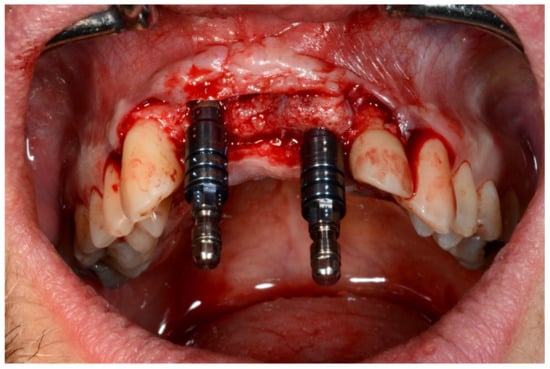

In November 2017, two guided dental implants were placed at sites # 12 and # 21 (Figure 7, Figure 8, Figure 9, Figure 10 and Figure 11).

Figure 7.

Surgical drilling guides temporarily supported by teeth on the right and left sides.

Frontal verification of the parallel placement of the implants.

Figure 11.